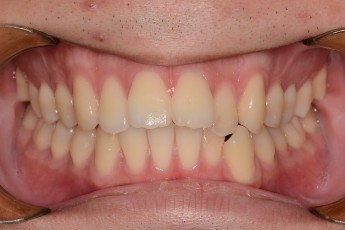

Before

After